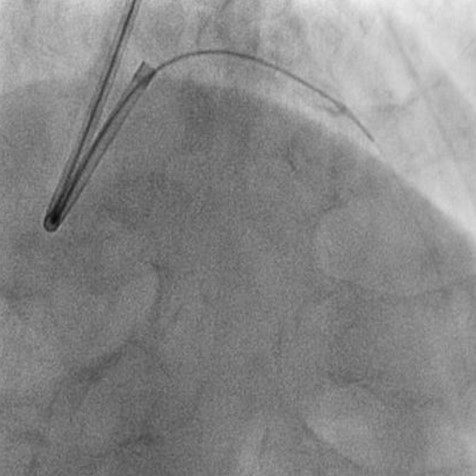

カテーテル治療の方法としては、手首か肘、あるいは足の付け根の動脈からカテーテルを挿入し、冠動脈の狭窄~閉塞部にワイヤーを通し、バルーンで病変を拡張し血流を改善~再開させ、必要に応じてステントを留置いたします。(図1~3)

図2.ステント留置